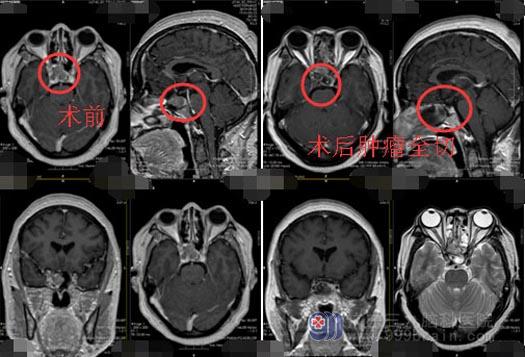

进一步头颅CT和磁共振检查提示:鞍区及鞍上囊实性占位病变,主管医生毕医生告诉郭大姐:鞍区占位的病变需要手术治疗,占位部位侵袭右侧海绵窦,颈内动脉已被推挤向中线移位,手术中需要保护垂体、视神经和颈内动脉,保护鞍隔完整,如果手术出现意外可引起颈内动脉海绵窦瘘,将会危及生命,很多意外难以预料。郭大姐吓得赶紧办理了出院。

排除手术禁忌症、完善术前准备后,神经外五科医生团队在全麻下为郭大姐实施了“内镜经鼻蝶鞍区侵袭性垂体瘤切除术+颅底重建术”。进入蝶窦后,发现鞍下壁被肿瘤破坏侵蚀。可见淡红色肿瘤,刮除窦内粘膜;导航再次定位,见右侧颈内动脉被肿瘤包绕,垂体位于左侧,鞍内肿瘤予以全切,切开海绵窦,切除海绵窦内肿瘤,颈内动脉无损伤,垂体保留,手术顺利。术后,郭大姐神志清楚,言语表达流利,神情目明,视力视野未见异常,四肢活动自如,未出现明显尿崩。术后复查头颅CT提示肿瘤全切。